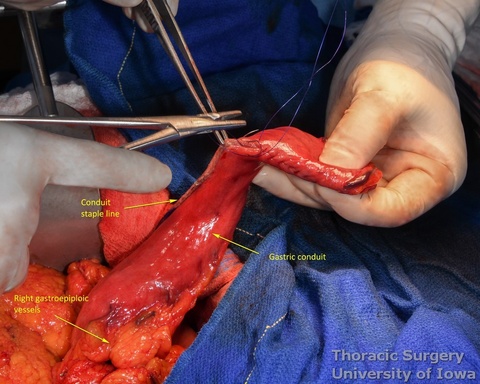

- At approximately the level of the third large vein (accompanying vagal “crow’s foot”) along the lesser curvature, lymphatic tissue and vessels are mobilized and divided to expose the gastric wall.

- Starting from the lesser curvature of the stomach, several stapler loads are sequentially fired towards the fundus of the stomach, thus creating a 4–5 cm wide gastric conduit and ensuring a 5 cm margin distal to the tumor. Depending on the thickness of the stomach, medium purple or thick black (alternatively blue or green, depending on manufacturer) loads are used.

- The gastric conduit stapler line is then oversewn with a running 4-0 (KP and JK) or 3-0 (EA) PDS.